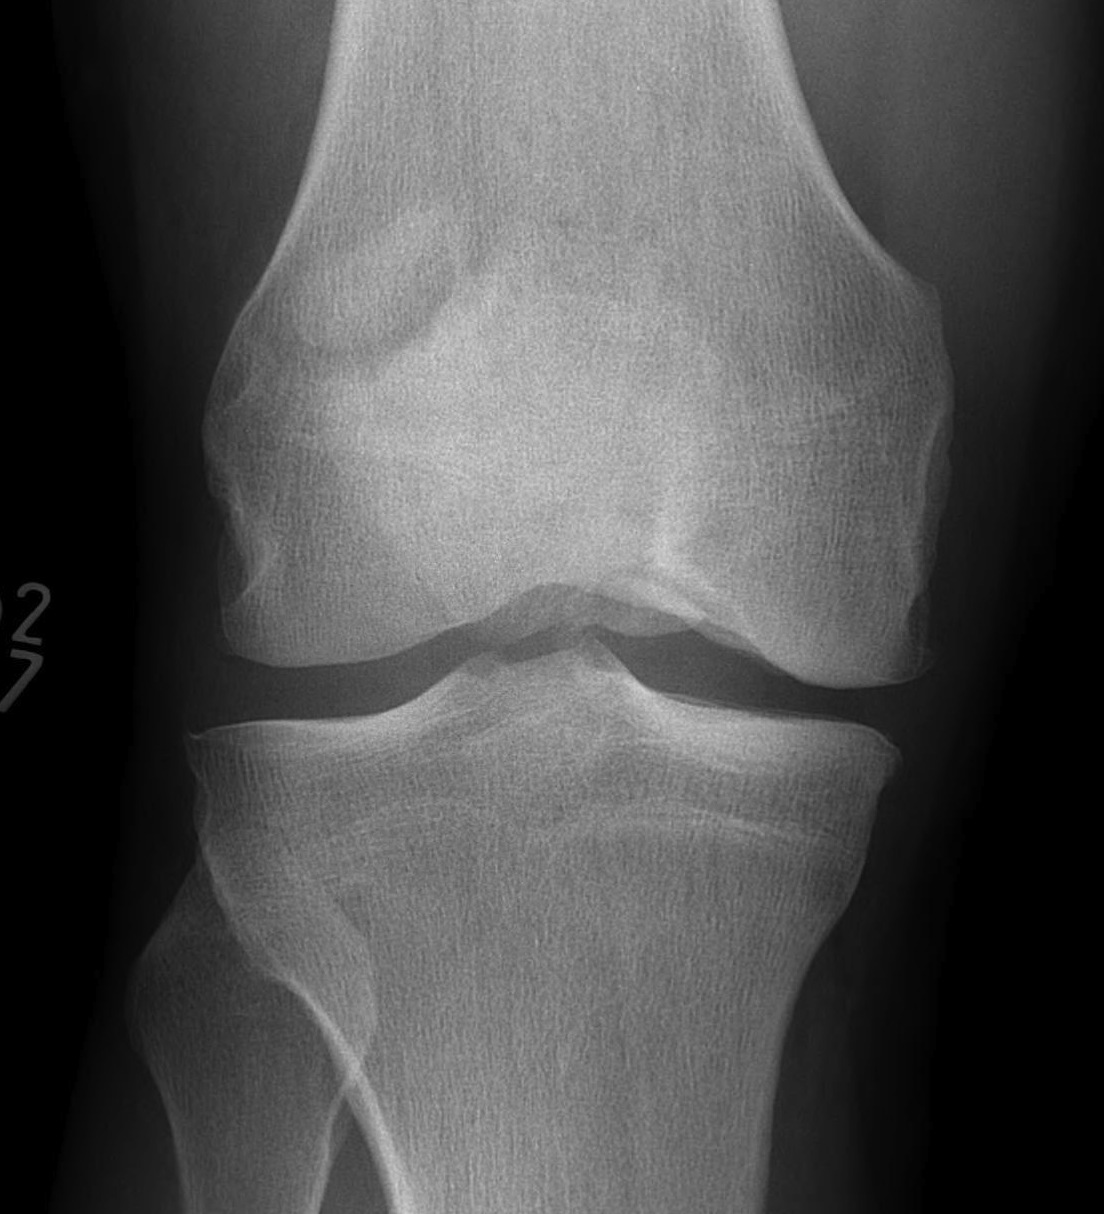

Xray